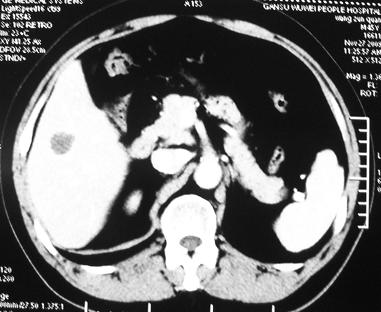

男 45岁。体检b超发现肝脏一低密度病变,怀疑是血管瘤,来ct检查。

ct平扫:在肝右后下叶一直径约2厘米的圆形低密度病变,ct值约32hu。

增强三期都未强化。后经mri检查,t1wi及t2wi为等信号,与肝脏等信号。